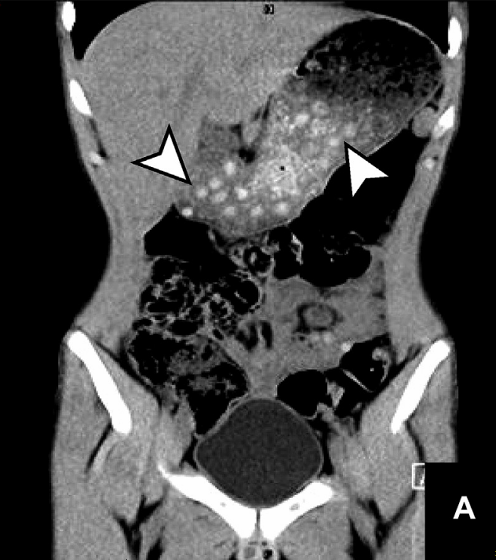

One of the strange effects of bubble tea is that tapioca balls can appear in internal organ scans when diagnosing car accidents or appendicitis . Because tapioca balls are denser than surrounding tissue and exhibit properties similar to kidney stones and gallstones, doctors may misdiagnose them. In the scan below, you can see tapioca balls in the area indicated by the arrow.